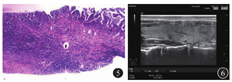

患者女,38岁,因"体格检查发现双肺多发占位3 d"于2019年10月21日入院。患者无咳嗽、咳痰、发热、盗汗等症状,体格检查示:甲状腺无肿大、压痛;全身浅表淋巴结未触及;呼吸运动正常,双肺呼吸音清,无干湿性啰音。入院后完善相关检查。超声检查示:甲状腺双侧叶实性结节[甲状腺影像报告和数据系统(throid imaging reporting and data system,TIRADS)分级为4a级,建议行超声引导下细针吸取(fine-needle aspiration)],甲状腺右侧叶囊实性结节(TIRADS分级为3级),见图1。胸部CT检查示:甲状腺双叶低密度结节,双肺多发结节,见图2。PET-CT检查示:双肺多发结节代谢较活跃,甲状腺双叶多发低密度结节代谢活跃。T-SPOT.TB示抗原A[早期分泌抗原靶-6(early secretory antigenic target-6,ESAT-6)]孔斑点数为56个,抗原B[培养滤液蛋白10(culture filtrate protein 10,CFP-10)]孔斑点数为50个;抗酸染色未见抗酸杆菌;血清三碘甲腺原氨酸(triiodothyronine,T3)、甲状腺素(thyroxine,T4)、游离三碘甲腺原氨酸(free triiodothyronine,FT3)、游离甲状腺素(free thyroxine, FT4)、促甲状腺激素(thyroid-stimulating hormone,TSH)均正常,结核特异性分泌抗原抗体、结核分枝杆菌抗体IgM及IgG均为阴性。行超声引导下甲状腺结节穿刺细针吸取细胞学检查(图3),在多普勒超声引导下以22 G穿刺针进入结节,反复提拉,快速对结节抽吸约10~15次,并旋转针尖,取病灶的不同部位,抽出物以液基固定送病理检查。采用无菌棉球覆盖穿刺部位,按压5~10 min以防出血。病理检查显示:甲状腺右叶下极肉芽肿性炎伴坏死,结核不除外,见图4;甲状腺左叶下极考虑结节性甲状腺肿;肺穿刺活组织病理检查示肉芽肿性炎伴坏死,倾向结核,见图5。结合临床病史,以及实验室、影像学检查,基本可以诊断为肺结核合并甲状腺结核。

予患者2HRZE/4HR标准方案(2个月强化期,4个月巩固期,H为异烟肼,R为利福平,Z为吡嗪酰胺,E为乙胺丁醇)治疗,患者可能发生的不良反应有肝功能损伤、超敏反应等。当出现药物不良反应时,可通过调整抗结核药物,选用氨基糖苷类抗菌药物或氟喹诺酮类药物替代一线抗结核药物。定期复查超声和CT。患者甲状腺的结核病灶在治疗5个月后明显缩小,9个月后消失,见图6。肺部的结核病灶5个月后缩小,但后期随访1年,CT检查仍提示双肺多发结节,较前变化不大。